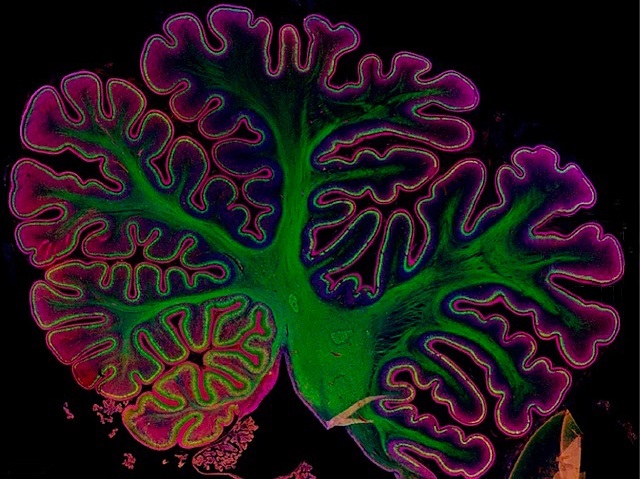

Details of Development

Single cell genetic and epigenetic activity analysed during human foetal cerebellar development creates an integrated spatiotemporal map